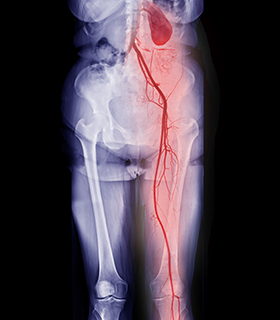

Peripheral Arterial Bypass

Surgical procedure to redirect blood flow around blocked arteries in the limbs, restoring circulation.